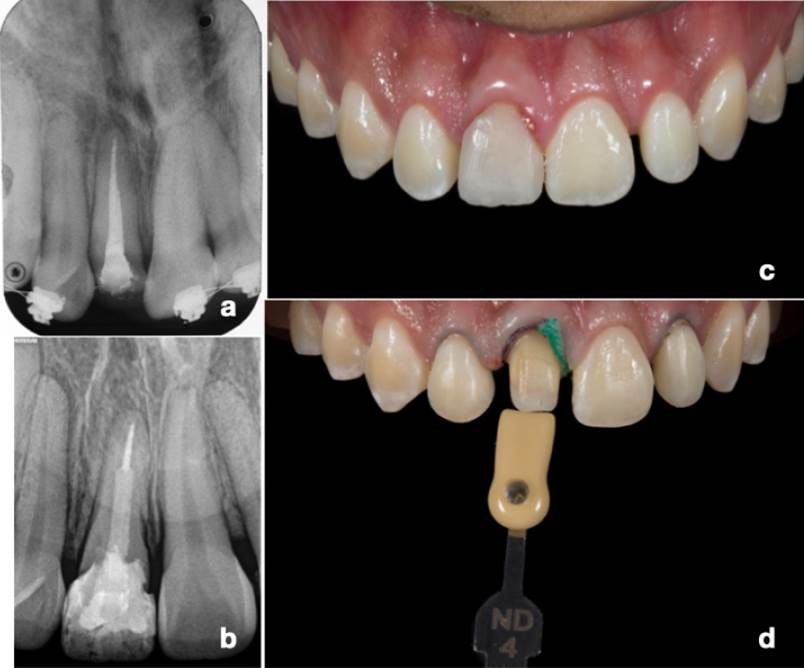

Después de 8 semanas de haber realizado la gingivectomía, se continuó con la rehabilitación post-endodóntica colocando un poste de fibra de vidrio (Kit Parapost Fiber Lux®, Coltène, Altstätten, Suiza), con reconstrucción de material resinoso de núcleos (ClearfilTM DC CORE PLUS, Kuraray Noritake Dental Inc., Okayama, Japón) y resina estratificada (ClearfilTM AP-X ES-2, Kuraray Noritake Dental Inc., Okayama, Japón) como provisional durante el tratamiento de ortodoncia (Figura 2.C) de acuerdo con la angulación de la raíz (Figura 2.D). En la Figura 3.A-B se muestran las radiografías tomadas antes y después del tratamiento. Por último, se continuó con la verticalización de la raíz del diente 11, así como la distribución mesio-distal de los espacios en la zona anterior, para la fase estética. Una vez que se alcanzaron las metas ortodónticas se refirió al paciente a rehabilitación bucal (Figura 3.C).

Figura 3 Avances del tratamiento. A. Radiografía final del tratamiento de conductos. B. Radiografía de la reconstrucción con estratificación temporal. C. Cicatrización del procedimiento quirúrgico. D. Toma de color de los núcleos

Se realizó la preparación de la corona del diente 11 con fresa de carburo y se realizó la hibridación dentinaria con técnica Resin Coatingn12 (ClearfilTM SE Bond Kit + ClearfilTM AP-X Esthetics Flow, Kuraray Noritake Dental Inc., Okayama, Japón) complementando las preparaciones para carillas de disilicato de litio (IPS e.max Press, Ivoclar Vivadent AG, Liechtenstein) de los dientes anteriores 12, 21 y 22, tomando color de núcleos (Figura 3.D) para la realización de las restauraciones (Figura 4.A). Para la cementación se realizó la reactivación del Resin coating con Óxido de Aluminio (Al2O3) a 50µm a 3.5 bar durante 5s con una distancia de 10mm13. Finalmente, se realizó la cementación con cemento largo plazo dual self-etch libre de aminas14 (PanaviaTM V5 Clear, Kuraray Noritake Dental Inc., Okayama, Japón) para garantizar la estabilidad de color transparente y compensar la atenuación del disilicato de litio en la pérdida de energía lumínica (Figura 4B-C).